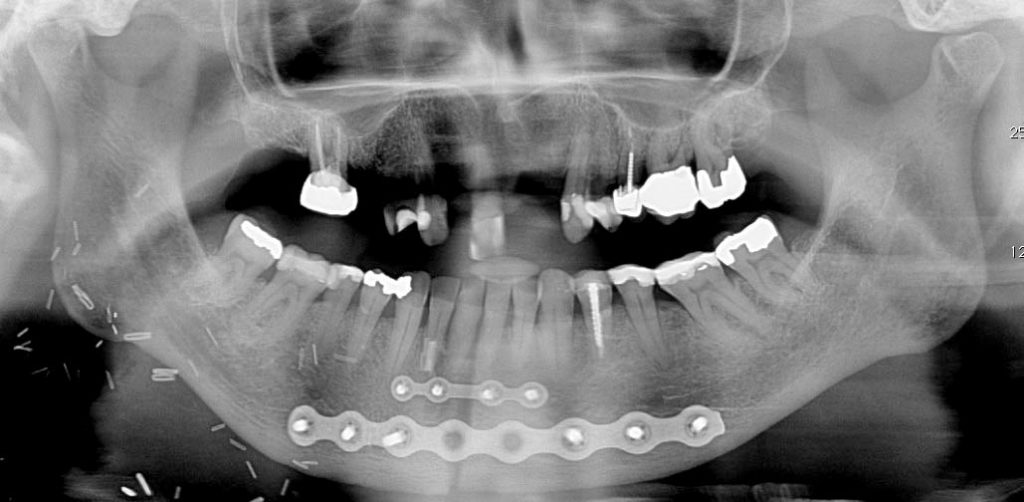

This is an example of a 78F patient who was treated surgically with a mandibulotomy procedure, partial glossectomy and post-operative radiation therapy for a squamous cell carcinoma of the tongue. It can be seen that the patient was unable to lift the tongue secondary to the surgery to optimize the panoramic radiograph emphasizing the airway shadow over the roots of the maxillary anterior teeth. Reapproximation of the sectioned mandibular segments by fixation with 2 titanium plates is evident. Complications that may arise include: loss of vitality and mobility of the teeth adjacent to the resection line, malocclusion and temporomandibular joint pain.